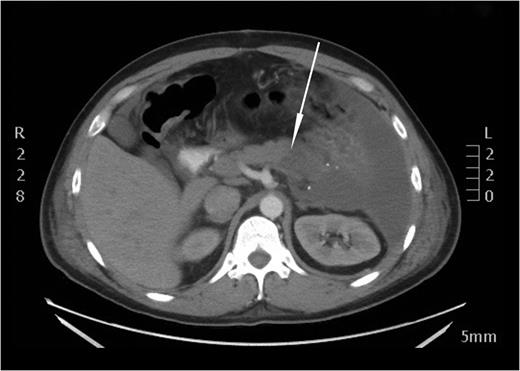

After the secondary survey, the patient was subjected to a computed tomography (CT) study, which showed a Grade IV splenic injury per the American Association for the Surgery of Trauma injury grading score with contrast extravasation (Fig. 1), a lower lobe contusion of the left lung, fractures of the IV and VI–XI ribs on the left side and bilateral iliac wing fractures. The pancreatic parenchyma was well perfused and homogenous in a portal venous phase CT-imaging (Fig. 2).

Axial view of the initial CT scan showing Grade IV splenic injury with contrast pooling in the peritoneal cavity.